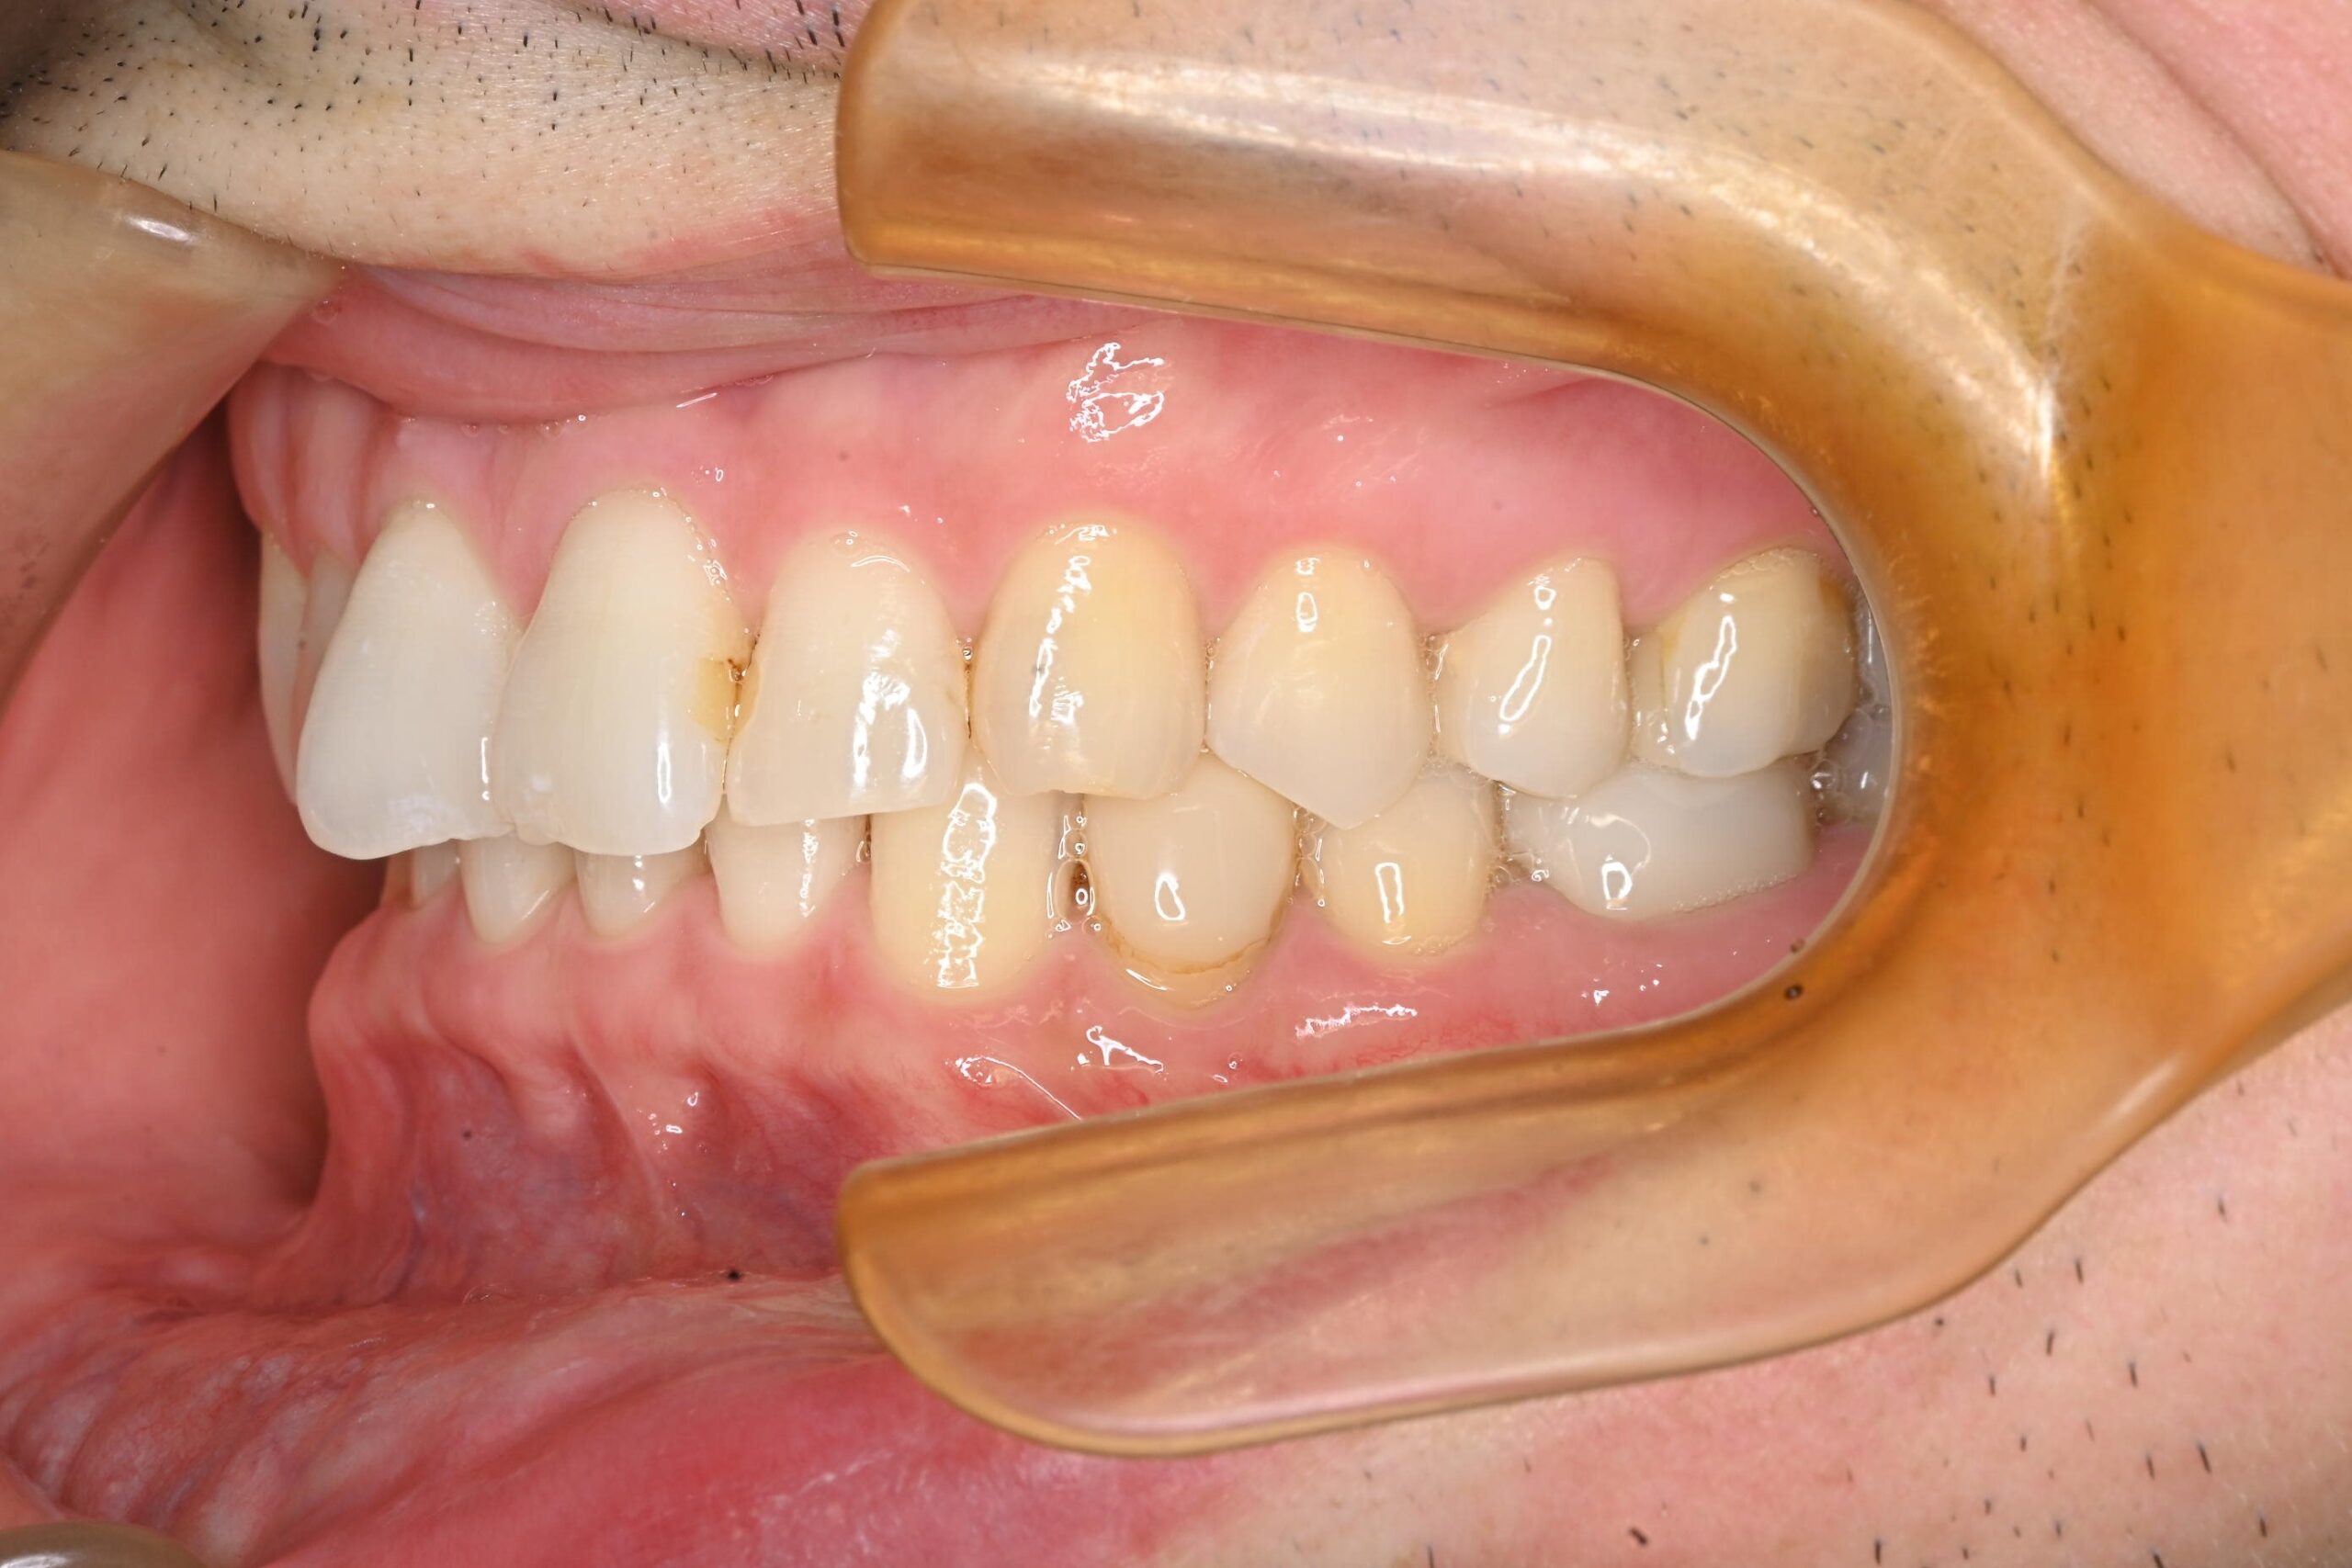

治療結果

全ての金属を非金属素材に置き換え、感染源も除去した結果、治療後は症状が落ち着いている状態が確認されました。 患者様はアレルギーやそれに伴う症状の悩みが大幅に軽減されたようで、非常に喜んでいただけました。

本症例では、金属アレルギーの懸念に加え、古い金属修復物の下に潜んでいた虫歯や感染源を全て取り除き、生体親和性が高く審美性にも優れた非金属素材に置き換えることができました。

患者様が長年抱えていたアレルギーや全身症状に関する悩みが軽減され、大変喜んでいただけたことは何よりでした。